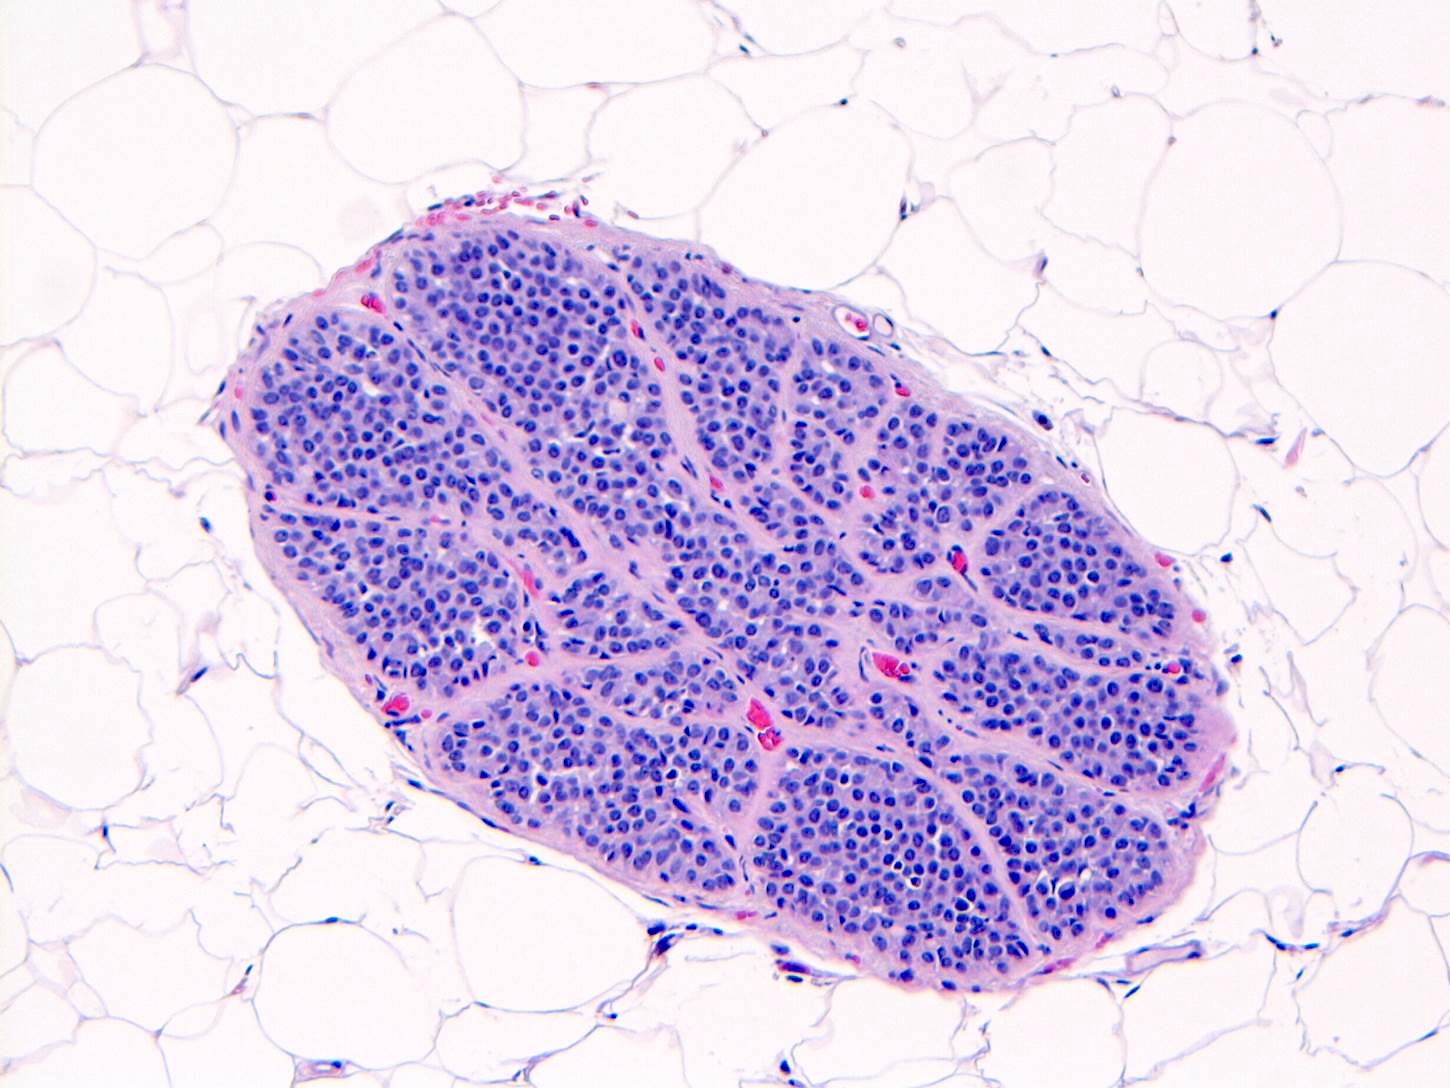

Microscopic (histologic) description

- LCIS involves the terminal duct lobular unit (TDLU), filling and distending acini

- > 50% of the acini in a TDLU must be filled and expanded to qualify as LCIS; otherwise, called atypical lobular neoplasia

- Lobular distention is defined as the presence of ≥ 8 cells in the cross sectional diameter of an acinus

- Involved lobules may be compared with uninvolved lobules to estimate the degree of distension

- Classic LCIS cells are monomorphic, evenly spaced, loosely cohesive and do not show polarization or gland formation

- 2 types of cells are described:

- Type A: nuclei are small to slightly enlarged (1 - 1.5x size of lymphocyte) with uniform round nuclei and inconspicuous nucleoli

- Type B: nuclei larger (2x size of lymphocyte), more abundant cytoplasm and more prominent nucleoli

- Type A and B cells can coexist in the same lesion

- Cytoplasm of LCIS cells is typically pale to lightly eosinophilic with indistinct cell borders

- In almost all cases of LCIS, at least some cells contain intracytoplasmic vacuoles or lumina, which may contain an eosinophilic globule; this feature is not specific to LCIS

- Outer layer of myoepithelial cells is retained in the acini and ducts involved but it may be attenuated

- Classic LCIS does not show significant nuclear pleomorphism or mitosis

Microscopic (histologic) images

Contributed by Anna Biernacka, M.D., Ph.D.